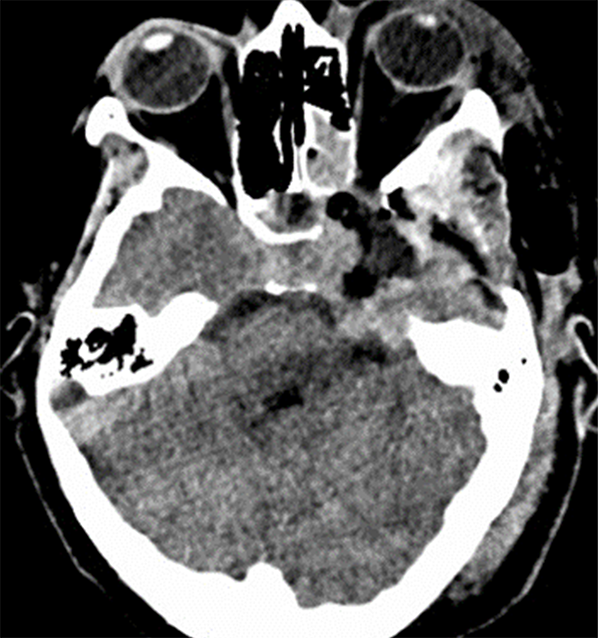

Treinta días luego de la cirugía nos volvió a consultar por presentar un síndrome febril y una colección en el sitio quirúrgico. Al examen físico, respecto al post-operatorio al momento del alta, se evidenció un aumento notable de la proptosis. Se realizó una tomografía computada (TC) que evidenció una colección epidural con realce luego de la inyección de contraste endovenoso y una lesión en seno cavernoso izquierdo de mayor tamaño al encontrado en la TC post-operatoria previa (Fig 2-Fig 3). Ante el aumento de volumen de la lesión previa se sospechó que el remanente tumoral se había abscedado. Se decidió realizar una toilette del sitio quirúrgico y una resección de la lesión. El hecho llamativo fue que el crecimiento del remanente tumoral no fue a expensas de un proceso infeccioso sino a expensas de proliferación neoplásica. La anatomía patológica evidenció que se trataba de un tumor maligno de la vaina de nervio periférico (TMVNP). Durante su estadía en la unidad de terapia intensiva (UTI), y como protocolo de nuestra institución, se realizó un hisopado para el SARS-COV-2 el cual resultó positivo. Como resultado de ello, su cuadro clínico fue empeorando progresivamente, evolucionando hacia una insuficiencia respiratoria que requirió asistencia respiratoria mecánica. La paciente falleció diez días después de la última intervención quirúrgica.

Figura 3:Tomografía Computada de encéfalo simple axial postquirúrgica al día 30 de la cirugía. Se evidencia aumento del tamaño tumoral, una colección epidural y un aumento de la proptosis.